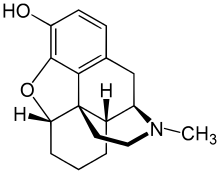

The pharmacodynamic response to an opioid depends upon the receptor to which it binds, its affinity for that receptor, and whether the opioid is an agonist or an antagonist. For example, the supraspinal analgesic properties of the opioid agonist morphine are mediated by activation of the μ1 receptor; respiratory depression and physical dependence by the μ2 receptor; and sedation and spinal analgesia by the κ receptor. Each group of opioid receptors elicits a distinct set of neurological responses, with the receptor subtypes (such as μ1 and μ2 for example) providing even more [measurably] specific responses. Unique to each opioid is its distinct binding affinity to the various classes of opioid receptors (e.g. the μ, κ, and δ opioid receptors are activated at different magnitudes according to the specific receptor binding affinities of the opioid). For example, the opiate alkaloid morphine exhibits high-affinity binding to the μ-opioid receptor, while ketazocine exhibits high affinity to ĸ receptors. It is this combinatorial mechanism that allows for such a wide class of opioids and molecular designs to exist, each with its own unique effect profile. Their individual molecular structure is also responsible for their different duration of action, whereby metabolic breakdown (such as N-dealkylation) is responsible for opioid metabolism.